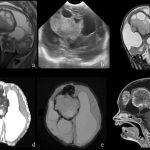

The intersection of neurosurgery and maternal-fetal medicine has seen remarkable progress in recent years, particularly with prenatal interventions for congenital neural tube defects like myelomeningocele (the most severe form of spina bifida). These advancements offer hope for improved neurological outcomes while carefully balancing maternal and fetal risks.

The landmark Management of Myelomeningocele Study (MOMS) in 2011 established that open fetal surgery before 26 weeks gestation significantly reduces the need for postnatal shunting for hydrocephalus, reverses hindbrain herniation, and improves motor function compared to postnatal repair. Since then, research in 2024–2025 has focused on refining techniques to minimize maternal complications, such as shifting toward fetoscopic repair—a minimally invasive approach using small incisions and endoscopes.

Recent studies highlight fetoscopic methods achieving comparable neurological benefits with lower risks of preterm labor and uterine dehiscence. For instance, multi-center reviews and single-institution series report higher rates of hindbrain herniation reversal and reduced CSF diversion needs, while innovations like human umbilical cord patches and standardized multi-layer closures are enhancing durability and outcomes.

Emerging areas include exploratory fetal interventions for isolated hydrocephalus (e.g., endoscopic third ventriculostomy in animal models) and stem cell-augmented repairs, though these remain investigational. Multidisciplinary teams involving maternal-fetal medicine specialists, pediatric neurosurgeons, and anesthesiologists are key to success, performed only in high-volume centers.